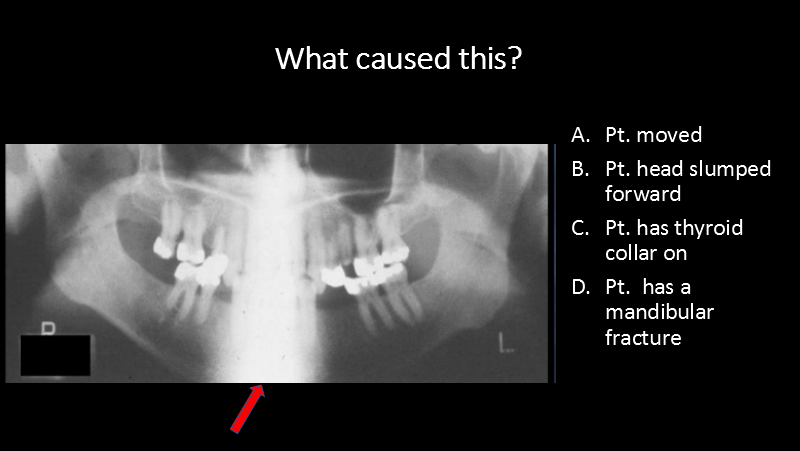

What caused this?

A. Pt. moved

B. Pt. head slumped forward

C. Pt. has thyroid collar on

D. Pt. has a mandibular fracture